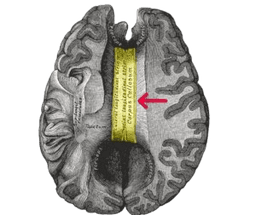

Corpus Callosotomy

Corpus Callosotomy is a surgical procedure to treat epilepsy. Epilepsy, which is a chronic medical condition, affects individuals for the long term and leads to recurrent seizures in both children and adults. Typically, the treatment is performed under the care of the best neurosurgeons in India. During the corpus callosotomy procedure, an incision is made through the brain's corpus callosum. The corpus callosum, which is a type of band of nerve fibers, joins the two halves of the brain (hemispheres) and relays messages from one hemisphere to the other. As a result, the corpus callosum prevents seizure signals from crossing back and forth between the two hemispheres, thus limiting the spread of seizure activity. This surgery is also known as callosal sectioning or brain splitting. -br Epilepsy surgery consists of various types, and corpus callosotomy is one of them. However, corpus callosotomy surgery is only recommended when antiseizure medications fail to relieve or treat the seizures effectively. In general, the entire procedure is performed under the supervision of experienced surgeons, involving a careful surgical cut of the band of fibers that join the two halves of the brain.